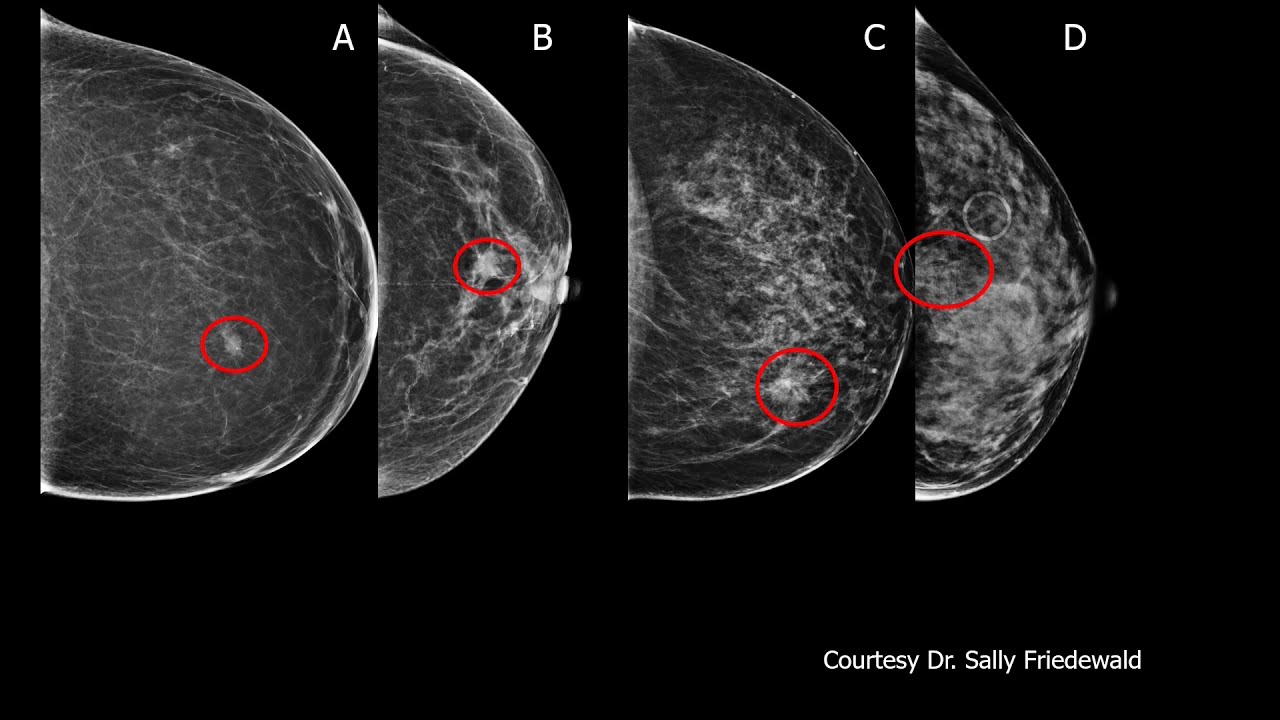

Screening Algorithms in Dense Breasts

Screening mammography reduces breast cancer mortality; however, performance and resulting benefits are reduced in dense breasts. Increased breast density also represents an independent risk factor for breast cancer. Digital breast tomosynthesis (DBT), ultrasound (US), MRI, molecular breast imaging (MBI) and contrast-enhanced mammography (CEM) each have demonstrated improved cancer detection in dense breasts compared to 2D-digital mammography (DM). Producing simultaneous reduction of recalls, DBT is the preferred mammographic technique. US further increases cancer detection after DM or DBT and reduces interval cancers, but results in substantial additional false positive findings. MBI improves cancer detection with effective radiation dose about four-fold that of DM or DBT, but still within accepted limits. MRI provides the greatest increase in cancer detection and decreases interval cancers and late-stage disease; abbreviated techniques will reduce cost and improve availability. CEM appears to offer performance similar to MRI, but further validation is needed. Dense breast notification will soon be the national standard: understanding performance of mammography and supplemental modalities is necessary to optimize screening for women with dense breasts. Read More: https://www.ajronline.org/doi/abs/10....

Presented by Wendie A. Berg, MD, PhD Professor of Radiology, U Pittsburgh School of Medicine, Magee-Womens Hospital of UPMC, Chief Scientific Advisor DenseBreast-info.org.